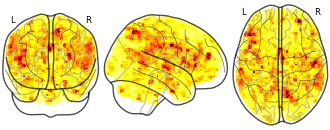

"name": "Multi_VBMsmaller_fMRIenhanced",

"description": "Multi-modal analysis in BPD. Brain regions exhibiting smaller gray matter and enhanced activation during emotion processing in BPD compared to healthy controls. Note: Results were thresholded at p<.0025. Note2: Results were updated (see Erratum for this publication).",

"name": "Multi_VBMsmaller_fMRIdecreased",

"description": "Multi-modal analysis in BPD. Brain regions exhibiting smaller gray matter and decreased activation during emotion processing in BPD compared to healthy controls. Note: Results were thresholded at p<.0025. Note2: Results were updated (see Erratum for this publication).",